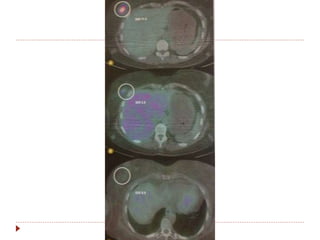

Avaliação de resposta com PET-CT

 Utilizar sempre o mesmo aparelho.

 SUV (standart uptake value).

 Diferencia tumor viável de necrose/fibrose.

 PERSIST 1.0

 Validade perante o RECIST: lesões novas

(confirmadas com TC) e não valor de captação.

Avaliação de respostacom PET-CT  Utilizar sempre o mesmo aparelho.  SUV (standart uptake value).  Diferencia tumor viável de necrose/fibrose.  PERSIST 1.0  Validade perante o RECIST: lesões novas (confirmadas com TC) e não valor de captação.